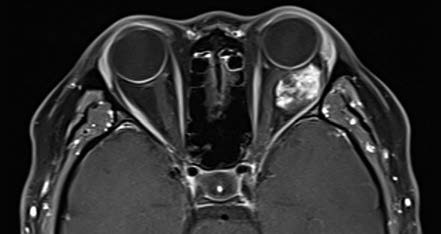

Figure 3 MRI imaging of a left orbital cavernous venous malformation

Progressive enhancement with early patchy enhancement.

On CT imaging, cavernous venous malformations typically appear well-demarcated and homogeneous in density. Signs such as optic nerve compression, displacement, and orbital cavity enlargement can be observed. CT imaging can also assess the degree of lesion adhesion. When fat is present at the posterior margin of the lesion, a triangular area of hypodense orbital fat is visible at the orbital apex on CT, suggesting minimal adhesion to surrounding tissues. Cavernous venous malformations without this hypodense orbital fat feature often exhibit significant adhesion. MRI findings show iso-intensity on T1-weighted images and hyperintensity on T2-weighted images. The hallmark of dynamic contrast-enhanced imaging is progressive enhancement, where small areas display early patchy enhancement that gradually becomes diffusely and homogeneously enhanced over time.